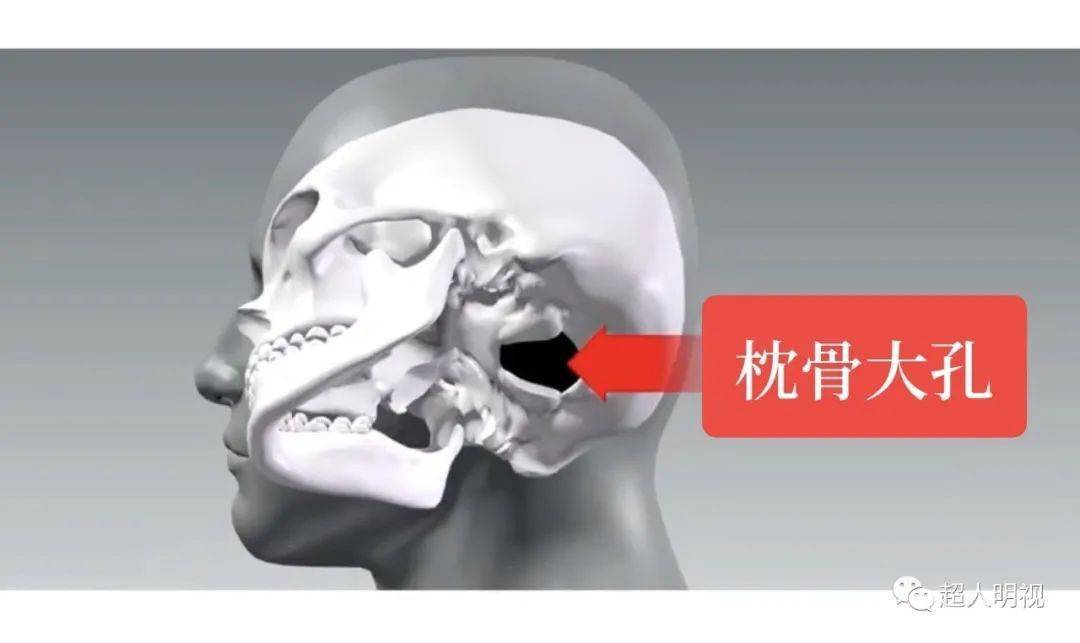

枕骨

血管及脑神经等重要结构受压和移位,被挤入硬脑膜的裂隙或枕骨大孔